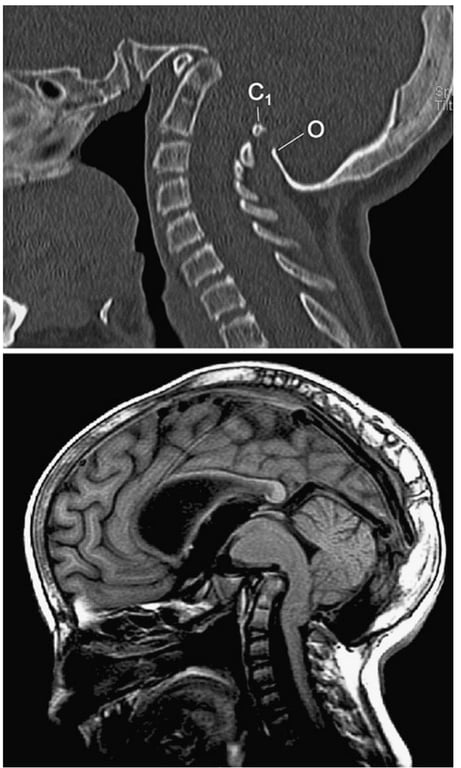

Sagittal CT shows extreme platybasia (NTB angle=180°), short clivus (<1.5 cm) and forward folding of the clivus–axis angle of Wackenheim (80°), causing lordotic tilt of the foramen magnum plane and plane of the occipital condyles, resulting in a retroflexed dens and severe basilar impression.

• Note violation of McGregor’s, Chamberlain’s and McRae’s lines by the dens. Also, extreme invagination of the opisthion (O) and high posterior C1 arch (C1).

• Sagittal MR shows distortion and compression of brainstem by both the dens and the opisthion